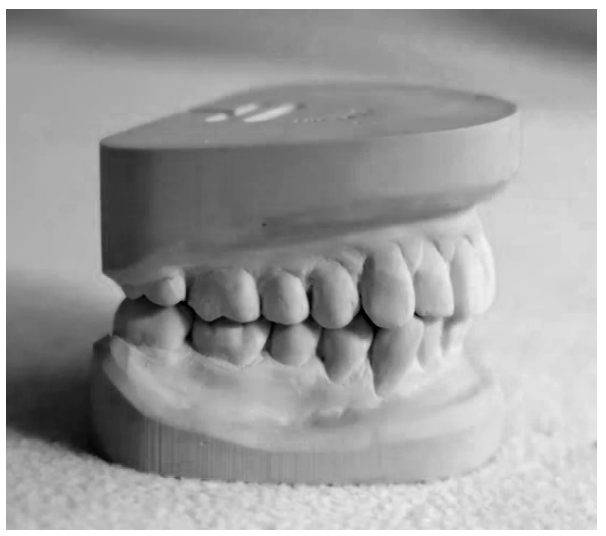

Analise a imagem a seguir:

Assinale a alternativa que corresponde corretamente à nomenclatura do dispositivo acima.